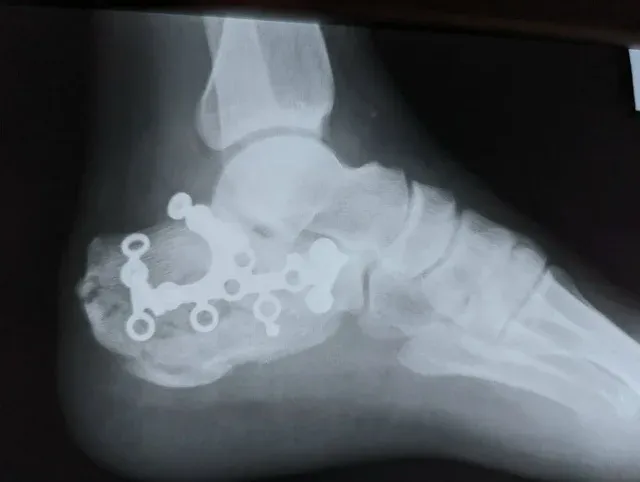

Областной центр спецмедпомощи продолжает помогать жителям региона с тяжёлыми травмами костей и суставов. В первую рабочую неделю нового года врачи провели операции 2 пациентам с переломом пяточной кости. Такие травмы считаются сложными и требуют точной работы хирургов.

Главная цель вмешательства – сохранить подтаранный сустав и вернуть ему подвижность. Если операцию не сделать, после такого перелома почти сразу появляется сильная боль. В итоге человеку приходится фактически «выключать» сустав, полностью лишая его движения, чтобы хоть как-то справляться с болью.

Врачи восстановили правильное положение костей и стабилизировали сустав. Сейчас самый сложный послеоперационный этап уже позади. Пациенты чувствуют себя стабильнее и начали проходить курс восстановления, который поможет постепенно вернуться к обычной жизни и опоре на ногу.